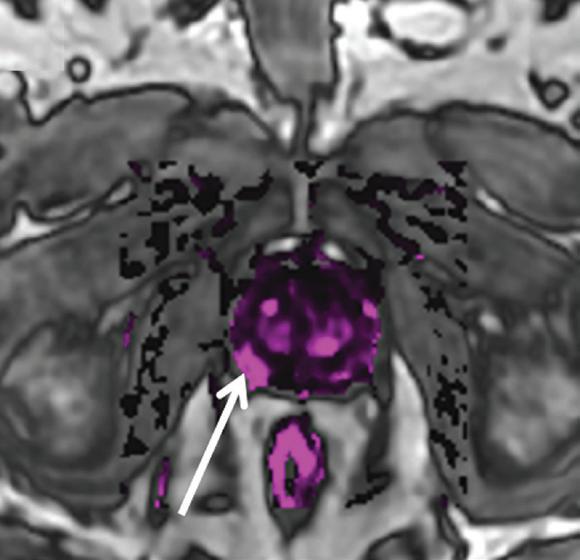

above: A 63-year-old man with right-side prostate cancer (shown by arrows) detected on 3T MRI of the prostate. Image D shows curves for average and worse pixels in the tumor. All images provided by Mount Sinai’s Department of Radiology and Translational and Molecular Imaging Institute.